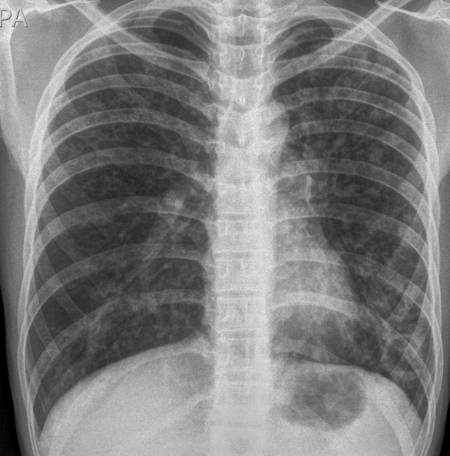

폐암을 조기 진단하는 가장 좋은 방법은 정기 검진이다. 다만, 환자 단체의 주장처럼 2년마다 전 국민을 대상으로 진행하는 건강검진 기본 항목의 '흉부 X선 촬영'은 폐암을 조기에 발견하는데 도움을 주지 못한다. 폐결핵이나 기관지염과 같은 다른 폐 질환을 잡는 데는 유용하지만 암은 예외다. 박동원 한양대병원 호흡기알레르기내과 교수는 "폐암 조기 진단에 흉부 X선이 무용하다는 것은 이미 여러 연구로 증명된 사실"이라 말했다. 보건복지부도 지난 1월부터 공단 건강검진 결과지에 "흉부 촬영 검사는 폐결핵 진단 검사이며 폐암 선별 검사는 아니다"는 문구를 삽입하고 있다.

이유가 뭘까. 첫째 낮은 해상도다. 흉부 X선은 크기가 1c㎝ 정도로 큰 폐암은 찾을 수 있지만 이보다 작은 건 발견하기가 힘들다. 건강검진의 목적이 '조기 진단'인데 커진 다음에야 발견할 수 있어 효용성이 적다.

둘째, 정확도가 낮다. 임형석 폐암환우회 이사는 "폐암 환자 중에서는 6개월간 기침과 흉통에 시달려 흉부 X선 검사를 받았는데 결과가 '정상'으로 나왔다가, 이로부터 반년이 지나 폐에 8㎝ 크기의 암이 뒤늦게 발견된 사례도 있다"고 말했다. 가능성 있는 일이다. 최천웅 교수는 "인체는 3차원인데 X선은 2차원 평면 촬영이라 다른 게 겹친 부위에 음영(그림자)이 생긴다"고 말했다.

박동원 교수는 "심장과 척추 등이 위치한 몸의 중앙 부위 폐암이 특히 잘 안 보인다"며 "주변 장기에 인접해 있거나 모양이 앞뒤로 길쭉한 경우, 혹은 딱딱하지 않은 간유리음영의 결절은 X선에서는 발견이 어렵기 때문에 흉부 X선으로 빨리 찾기 어려운 경우가 존재한다"고 했다.